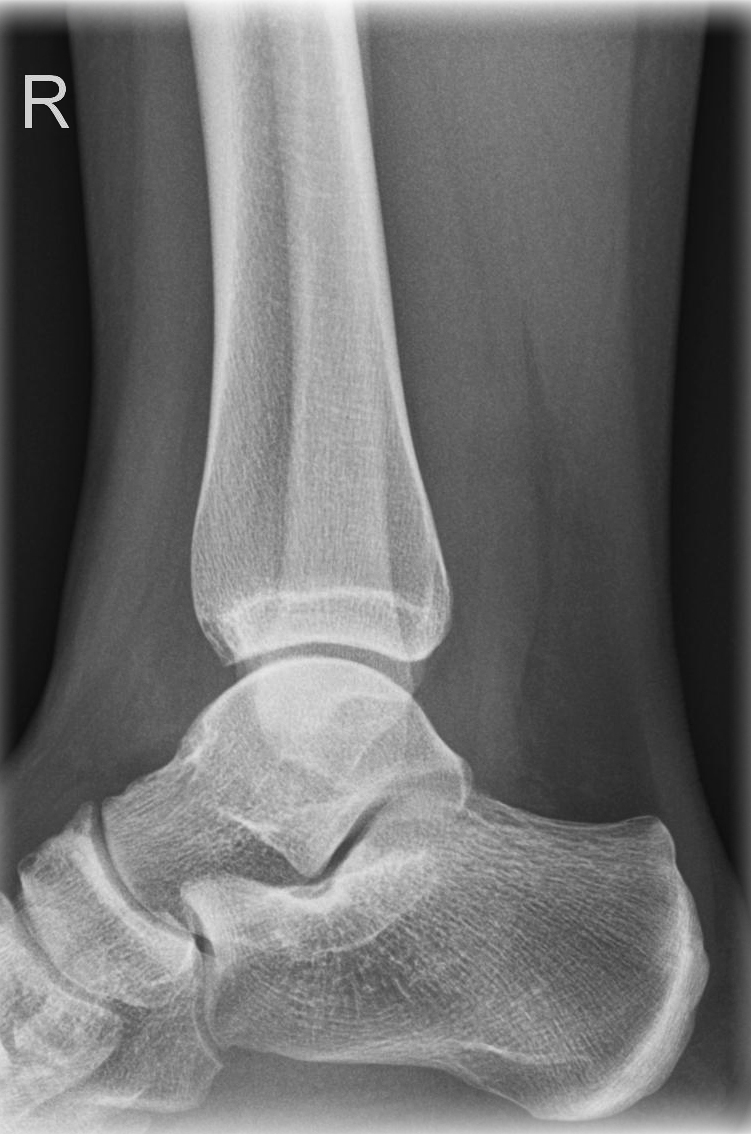

Oberes Sprunggelenk a.-p. (1. Ebene)

Technik

Indikation

Fraktur, Bandverletzungen, Luxation

Lagerung

sitzend/ liegend auf Tisch

gestreckte Bein nach innen rotieren, sodass Malleolus medialis und lateralis auf einer Höhe sind

(ca. 15-20° - Zeigefingertest)

Fuß anziehen, möglichst senkrecht zum Unterschenkel

Zentralstrahl

senkrecht

Querzentrierung: Gelenkspalt

Längszentrierung auf Objektmitte

Einblendung

proximal 5 QF ab ZS, lateral 1 QF

Qualitätskriterien

Frei einsehbares oberes Sprunggelenk, insbesondere im Bereich von Innen- und Außenknöchel und der tibiofibularen Syndesmose.